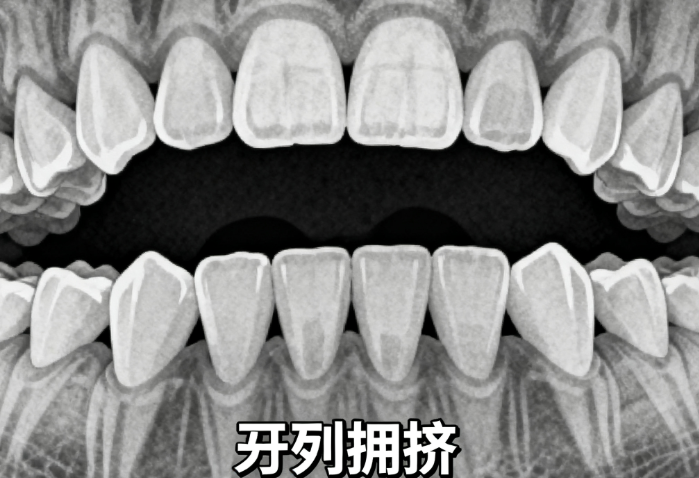

你是否正在为牙齿矫正而烦恼,却不知道SGTB矫正器每天该戴多久才能达到理想疗效?其实,牙医列出了3个关键时间点,20小时是基础,超过22小时疗效更好。www.59w.net接下来,我们将围绕SGTB矫正器每天戴几个小时,为你详细分析不同情况下的佩戴要求、佩戴方法、注意事项以及治疗周期等内容。